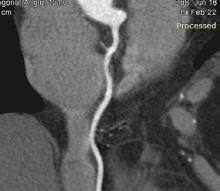

Imagistica avansată, în special cea de perfuzie, a revoluționat tratamentul AVC ischemic acut prin extinderea ferestrei terapeutice și optimizarea selecției pacienților pentru terapii de revascularizare (Inoue & Toyoda, 2021). Această tehnică, denumită angio-CT, permite evaluarea viabilității țesuturilor cerebrale, identificând regiunile de penumbră ischemică care pot fi salvate prin intervenții rapide

(Halil, 2023). Această abordare este crucială în ghidarea deciziilor privind tromboliza intravenoasă și trombectomia mecanică, mai ales în situațiile în care prezentarea pacientului depășește fereastra de timp tradițională pentru intervenție (Halil, 2023).

Studiile recente evidențiază rolul crucial al neuroimagisticii în diagnosticul rapid și precis al AVC, având un impact direct asupra selecției pacienților pentru terapii de urgență (Abdalkader et al., 2023), (Byrne et al., 2020). Această abordare este esențială pentru optimizarea rezultatelor clinice și minimizarea sechelelor neurologice pe termen lung, dat fiind că timpul este un factor determinant în recuperarea post-AVC (Săceleanu et al., 2023). În cazul AVC ischemic, identificarea rapidă a ocluziei vasculare și a țesutului cerebral recuperabil prin tehnici avansate de imagistică, permite inițierea tratamentelor trombolitice sau endovasculare în fereastra terapeutică optimă, conform ghidurilor internaționale (Nael et al., 2019) (Radwan, 2021). În acest context, angio-CT-ul cranio-cerebral se dovedește a fi un instrument indispensabil pentru detectarea ocluziilor vaselor mari și pentru ghidarea deciziilor terapeutice (Almekhlafi et al., 2019). Implementarea AI, în special a rețelelor neuronale convoluționale, în analiza imaginilor CT promite o accelerare semnificativă și o standardizare a diagnosticului, depășind limitările legate de expertiza radiologului și variabilitatea interpretării (Abdi et al., 2025). Această tehnologie avansată permite detectarea rapidă a anomaliilor subtile și cuantificarea caracteristicilor țesuturilor, îmbunătățind acuratețea diagnostică și promptitudinea intervenției (Broocks & Meyer, 2023). În plus, modelele de învățare profundă, antrenate pe seturi mari de date, pot identifica chiar și infarctele mici, pot evalua volumul leziunilor și pot prezice răspunsurile la tratament (Soun et al., 2020), (Brugnara et al., 2023). Integrarea AI în neuroradiologie oferă soluții inovatoare pentru diagnosticarea și gestionarea urgențelor neurologice, cum este AVC (AbuAlrob & Mesraoua, 2024), iar radiologul trebuie să aibă abilitatea de a corela datele AI cu cele clinice pentru un rezultat cat mai rapid posibil în urgență.